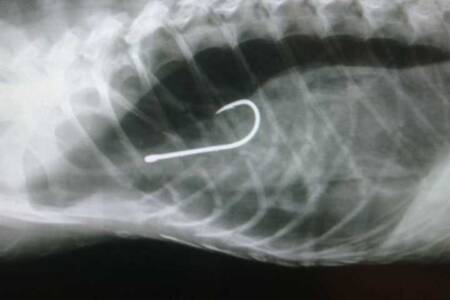

Pesquisadores denunciam a existência de armadilhas que estão ferindo e matando jacarés no Espírito Santo. O caso mais recente aconteceu no município da Serra (ES). Um jacaré foi encontrado preso em um engasgo, armadilha que contém um fio e um anzol.

Após o salvamento, o jacaré precisou realizar uma cirurgia para a retirada do anzol alojado em seu tórax, mas devido aos danos causados pelo petrecho o animal não resistiu.